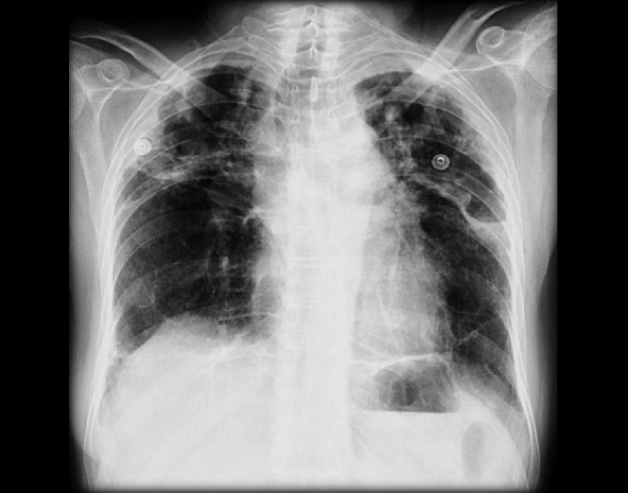

Hình ảnh chụp X-quang của người lao động khi mắc bệnh bụi phổi silic

– Để kiểm tra các bệnh bụi phổi, doanh nghiệp có thể bổ sung thêm đo chức năng hô hấp, xét nghiệm công thức máu, chụp X-quang tim phổi, test phục hồi phế quản,…

Chụp X-quang là phương thức hiệu quả giúp kiểm tra các bệnh lý liên quan đến phổi của người lao động ngành may